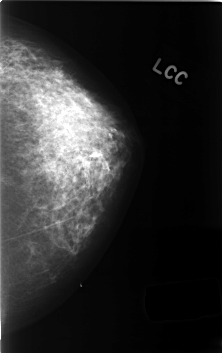

C_0413_1.LEFT_CC

LEFT_CC LINES 4584 PIXELS_PER_LINE 2880 BITS_PER_PIXEL 12 RESOLUTION 50 NON_OVERLAY